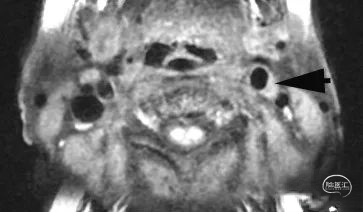

图3 头部磁共振ASL序列可见左额叶脑血流关注下降。说明左侧半球有缺血表现。

图4 颈动脉高分辨率磁共振可见左侧颈内动脉起始部有明显斑块形成,如箭头所示。颈动脉狭窄程度约50%。这与图1中CTA显示的狭窄程度(20%)差异很大。